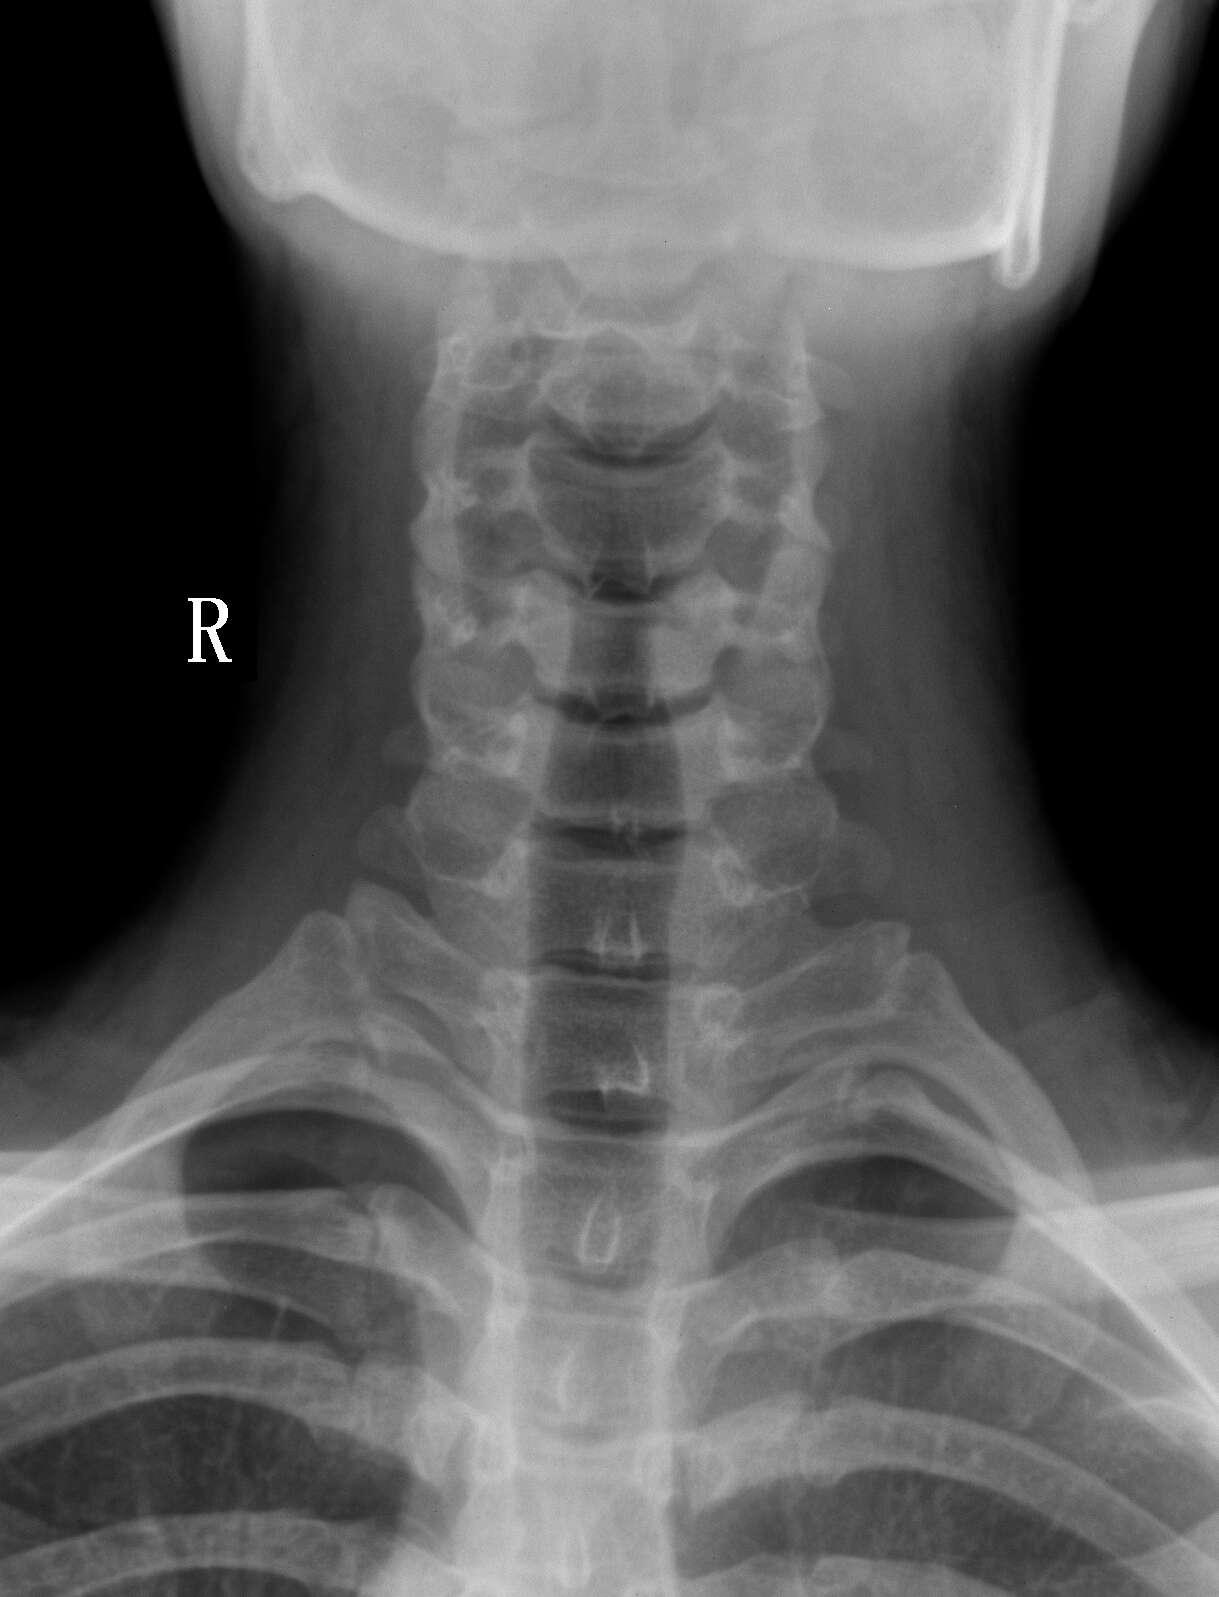

患者,男性,20y,常脖子酸痛来检

颈椎正侧位骨质未见异常。